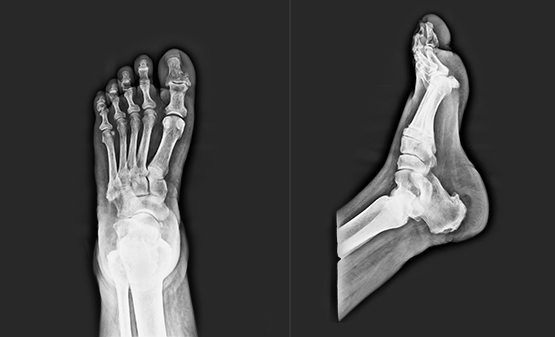

Digital Foot X-ray

An X-ray is a common imaging test that has been in practice since decades. X-rays provide doctors with an inside view of the body, without necessitating an incision. These images prove instrumental in diagnosing, monitoring and treating many medical conditions. At Aster, we have the latest Digital X-ray technology offering hi-definition imaging.